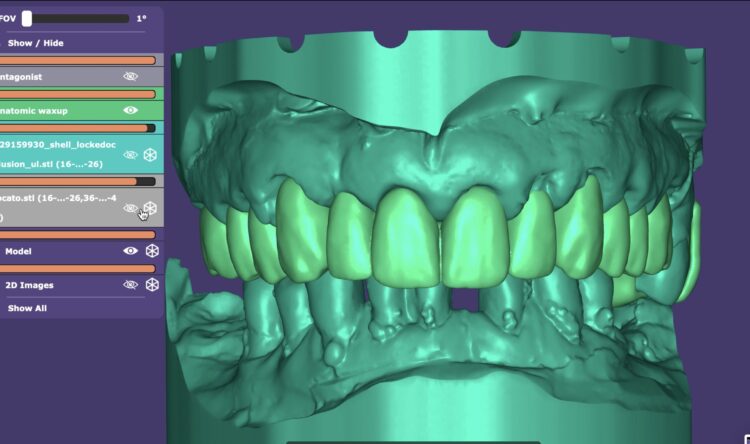

When ready, the surgical planning involved a fully digital, prosthetically-driven workflow, with full dentist and dental technician collaboration. Intraoral scans (IOS) were merged with the DICOM data from the CBCT to optimise data capture and facilitate an accurate digital plan for implant placement and prosthesis design. The digital files and photographs were imported into a Digital Design Software (EXOCAD) and a personalised, facially-driven tooth library was used to perform an initial virtual wax-up.

The use of a surgical guide for the accurate and precise placement of the dental implants was chosen in this case. The positions and angulations of the implants were planned according to the ideal virtual wax-up that was produced. We decided to create a tooth-supported acrylic guide for fully guided surgery, supplemented by bone-fixed anchor pins for enhanced stability. The most appropriate teeth for this were identified during this planning phase.

After four months, an IOS impression was executed and a digital dataset created superimposing the soft tissue, implant scan bodies, antagonist and temporary prosthesis scanning files. To avoid any inaccuracy in scalloped interface reproduction due to quick collapse of the gingival tissue, the provisional prosthesis was scanned both intraorally and extraorally, capturing its overall contour and, in particular, the transmucosal surface at the pontic sites and emerging profiles.

A titanium substructure was digitally designed (Bridge Base by Atlantis) taking into consideration the functional and aesthetic virtual wax-up and emergence profile as the FP1 provisional prosthesis shaped it. This metal substructure was anatomically shaped at the gingival and occlusal sides in order to tightly adhere at the soft tissue interface leaving at least 2mm of clearance for the zirconia superstructure.

Based on the digital design and copying the approved provisional prosthesis, a zirconia overlay was milled. The overlaying zirconia superstructure was digitally designed to fit the metal substructure, accomplish a flawless finish line, avoid any undercuts and verify the path of insertion, thus facilitating the bonding procedures. The zirconia superstructure was bonded with the titanium substructure using a self-curing luting composite. The final polished screw-retained prosthesis was delivered and torqued to 30Ncm and the radiographic assessment was executed.